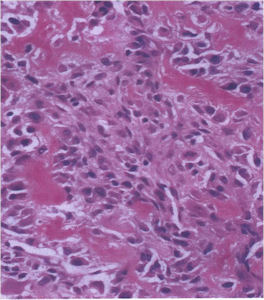

Aggressive Osteoblastoma

- Aggressive osteoblastoma is a distinct rare type of osteoblastoma that has a much more aggressive local behavior than a conventional osteoblastoma. They have a higher chance for local recurrence after removal.

- There has been controversy about the true existence of this type of tumor and whether these tumors are actually low grade osteosarcomas.

- They have a similar appearance microscopically as a conventional osteoblastoma except the osteoblasts are twice as large and have an epithelioid quality with abundant eosinophilic cytoplasm (Epithelioid Osteoblasts).

- Aggressive osteoblastoma is a borderline lesion lesion between osteoblastoma and osteosarcoma. It is not a precursor to osteosarcoma. It does not metastasize.

The differential between osteoid osteoma, conventional osteoblastoma and aggressive osteoblastoma is based on size and the presence of epithelioid osteoblasts. Can have epithelioid osteoblasts in osteoid osteoma and conventional osteoblastoma but they do not occur in cohesive sheets that fill intertrabecular spaces